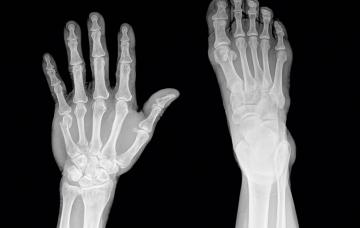

Qué es una fractura de dedo y qué puede causarla

Trabajando o practicando deportes los dedos pueden sufrir lesiones, como una fractura. Conoce los primeros auxilios a emplear en caso de romperte un dedo.

Signos y síntomas de una fractura de dedo

El síntoma común en una fractura de uno o varios dedos es el dolor agudo, que suele acompañarse de temperatura alta y sensación de ardor en la punta del dedo.

Qué hacer en caso de fractura de dedo

Estas medidas de primeros auxilios ayudan a tratar una fractura de dedo hasta que pueda solicitarse atención médica. Esto es lo que se debe hacer y lo que no.